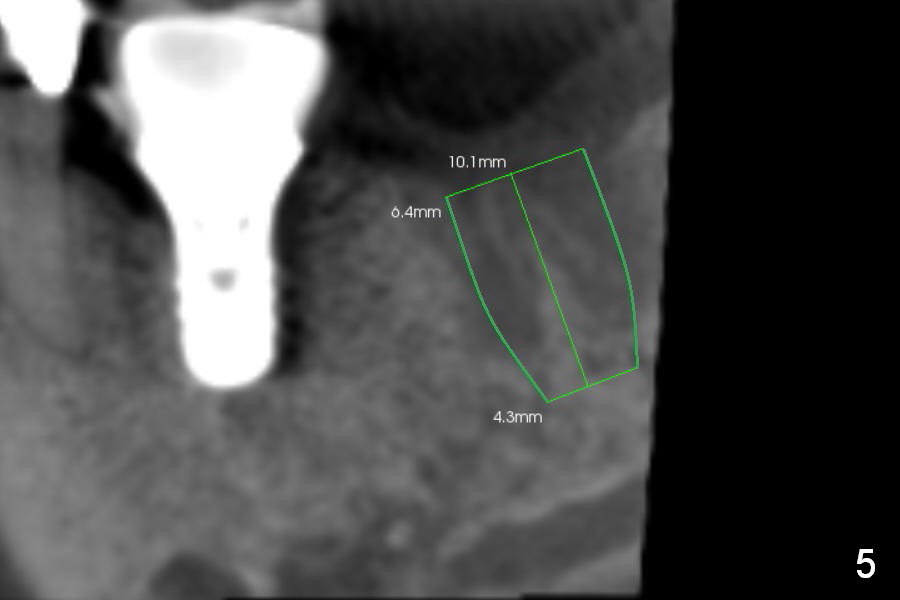

Preop CBCT shows that a 6.4x10 mm implant is appropriate if placed in the middle of the socket (septum), 6 mm from the crown of #30 (Fig.5). Coronal section confirms that because of the lingual slope of the socket, osteotomy should be placed lingually (Fig.6 red line). Three-D image is shown in Fig.7.